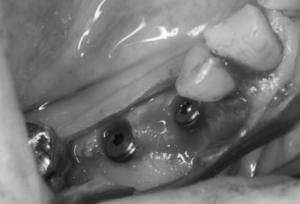

2つ目のケースは下顎の大臼歯にインプラント治療を行なった症例です。

ブリッジしてある状態でしたが、手前の歯は残念ながら保存が出来ないほど崩壊しておりました。

奥歯(写真でいう左下の歯)も抜歯の適応ではありましたが、全く症状がないため、ひとまずはブリッジをカットして保存することとなりました。欠損部分にはインプラント治療を行いました。

抜歯を行い、骨の回復を待ってから、インプラントを設置していきます。

インプラント設置後、3ヶ月で仮歯を入れて、その後、最終の歯を取り付けていきます。